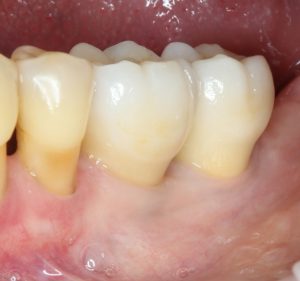

Но это еще не самое веселое. Допустим, мы решили проблему соединения «имплант-абатмент», у нас нет проблем с люфтами, а сам имплантат настолько хорошо интегрировался, что способен любую нагрузку в любом направлении. Возникает другая проблема — размер супраструктуры и соответствие ее нормальной биологической длине коронки зуба:

На фотографии выше, коронки опираются на обычные импланты, но даже в этом случае увеличение высоты супраструктуры усложняет гигиену и требует более пристального дальнейшего наблюдения. С ультракороткими имплантами, если честно, всё еще хуже.

Как будет выглядеть такая конструкция? Какой длины будут коронки? Возможно, на эстетику даже можно забить, ведь для некоторых людей красота зубов в боковом сегменте челюсти за пределами эстетически значимой зоны не так важна, но… как быть с уходом за протетической конструкцией и ежедневной гигиеной? Ведь, чем больше по размеру протез, тем сложнее за ним ухаживать. Тем больше мест, где может остаться зубной налет, а это, как вы понимаете, может привести к очень неприятным последствиям — периимплантиту, что для ультракоротких имплантов очень критично. А застревание пищи между протезом и десной? Можно ли назвать это «повышением качества жизни пациента»? Вряд ли.